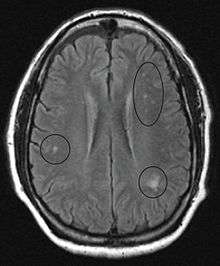

In the brain itself, changes are less severe: They occur as small sources of nervous fibers decay and accumulation of astrocytes, usually subcortically located, and also round hemorrhages with a torus of glial cells. Pathological changes can be noticed as well in the posterior roots of the cord and, to lesser extent, in peripheral nerves. Abnormalities might be observed in MRI.[41]